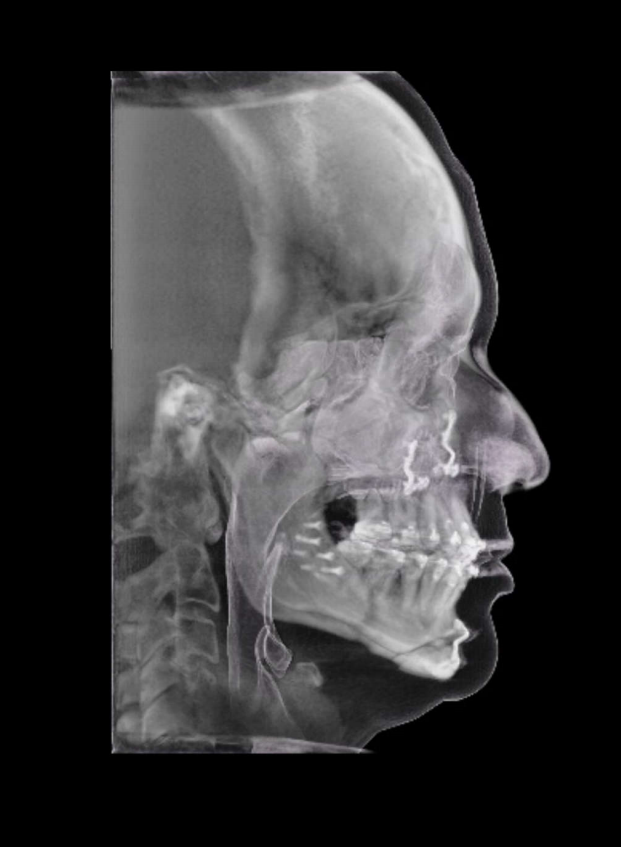

TC de face (do Hióide à Glabela), reconstrução 3D do tecido ósseo, radiografia panorâmica, telerradiografia lateral com traçado, cortes transversais e axial de maxila e mandíbula e arquivo DICOM- entregue em pasta de Pvc.

TC de face (do Hióide à Glabela), reconstrução 3D do tecido ósseo, radiografia panorâmica, telerradiografia lateral e frontal com traçado, cortes transversais e axial de maxila/mandíbula e arquivo DICOM – entregue em pasta de Pvc.

TC de face (do Hióide à Glabela), reconstruções 3D do tecido mole/ósseo/vias aéreas, radiografia panorâmica, telerradiografia lateral e frontal com traçado, cortes transversais e axial de maxila/mandíbula, ATM e arquivo DICOM – entregue em pasta e caixa de Pvc.